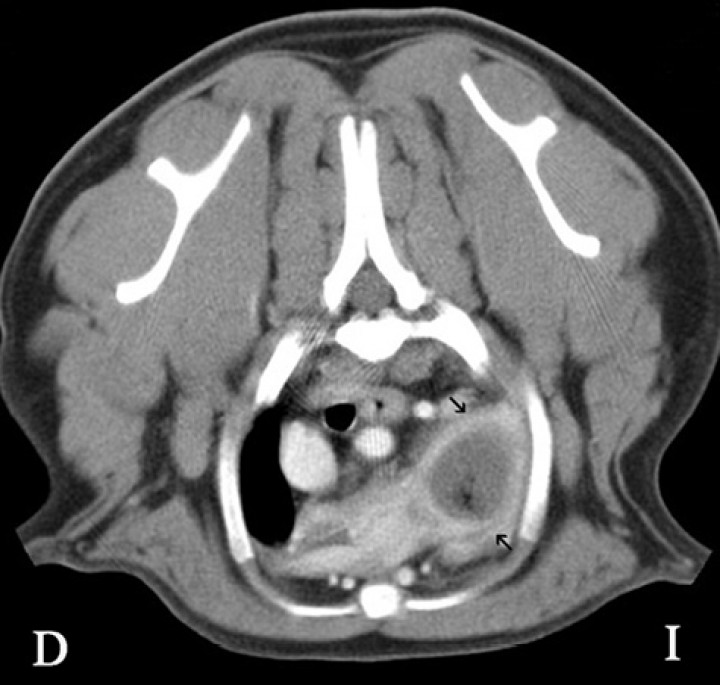

En el caso clínico que se presenta, la TC de la cavidad torácica evidenció una interrupción abrupta del bronquio lobar craneal izquierdo, observándose el lóbulo pulmonar craneal izquierdo (porción craneal y caudal) completamente consolidado con una pequeña zona enfisematosa en su porción más craneal, estando aumentado de tamaño y ocasionando una leve desviación hacia la derecha del mediastino craneal (Fig. 3). Tras la administración de contraste, el lóbulo presentó un realce en anillo con una zona central que no se realzaba con el contraste, siendo compatible con un área de necrosis o la formación de un absceso (Fig. 4).

<p>Imagen de tomografía computarizada (TC) del tórax en plano transversal en ventana de tejido blando tras la administración del contraste. Se visualiza en la zona del lóbulo craneal izquierdo un realce en anillo (flechas negras) con una zona central sin realce.</p>

Imagen de tomografía computarizada (TC) del tórax en plano transversal en ventana de tejido blando tras la administración del contraste. Se visualiza en la zona del lóbulo craneal izquierdo un realce en anillo (flechas negras) con una zona central sin realce.

La TC es la herramienta de imagen de elección para el estudio del parénquima pulmonar. En los casos con torsión pulmonar, esta técnica avanzada de diagnóstico por imagen permite la visualización de bronquios con una terminación abrupta, una posición anormal del lóbulo pulmonar y la falta de realce de contraste en todo el lóbulo pulmonar agrandado,[ Davies JA, Snead EC, Phar JW. Tussive syncope in a pug with lung-lobe torsion. Can Vet J, 2011; 52: 656-660. [PubMed] , Seiler G, Schwarz T, Vignoli M, Rodriguez D. Computed tomographic features of lung lobe torsion. Vet Radiol Ultrasound, 2008; 49:504-508. [PubMed] ] siendo signos patognomónicos del proceso. Estos cambios fueron evidenciados en nuestro paciente, junto con una leve efusión pleural, la cual es indicativa de cronicidad del proceso en pacientes con torsión pulmonar.[ Davies JA, Snead EC, Phar JW. Tussive syncope in a pug with lung-lobe torsion. Can Vet J, 2011; 52: 656-660. [PubMed] ]